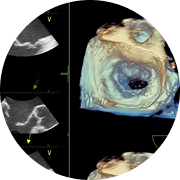

Imagerie cardiaque avancée pour un diagnostic détaillé.

Ancien Imageur cardiaque au CHU Dupuyrien Limoges-France (réalisations de plus de 500 échographie cardiaque écho de stress et de écho trans oesophagienne avec certification)

Fellowship en imagerie multimodale au CHU PONTCHAILLON Rennes avec la réalisation de plus de 80scanners et plus de 80 IRM cardiaque.